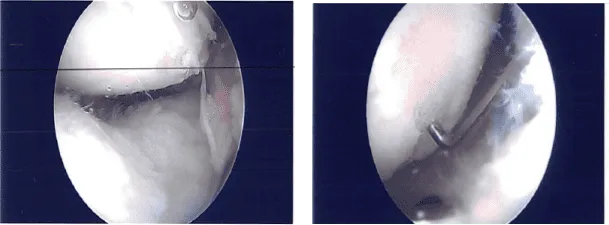

Se indujo anestesia general al paciente y se aplicó torniquete en la parte baja del muslo izquierdo. Se realizó un drapeado y un vendaje separados con restos y se encontraron muchos restos en la articulación de la rodilla. Había artritis patelofemoral.

Había deshilachado en el borde interno del menisco medial. Había daño de OA grado 1 a grado 2 en el cóndilo femoral. El menisco estaba desbridado hasta un margen estable. Se realizó una condroplastia en el cóndilo femoral medial.

El endoscopio se introdujo en la muesca intercondilar y se introdujo en el cóndilo femoral lateral, encontrando deshilachamiento del margen interno del menisco lateral junto con la pequeña rotura. Se realizó una meniscectomía parcial del borde interno.

La atención se centró en la articulación patelofemoral donde había daño osteocondral, de grado 1 a grado 2 en la superficie articular medial de la rótula. Estaba desbridada hasta un margen estable. Había un gran daño osteocondral, de grado 2 a grado 3 sobre la troclea, que también se desbridó. Se tomaron las fotos finales.